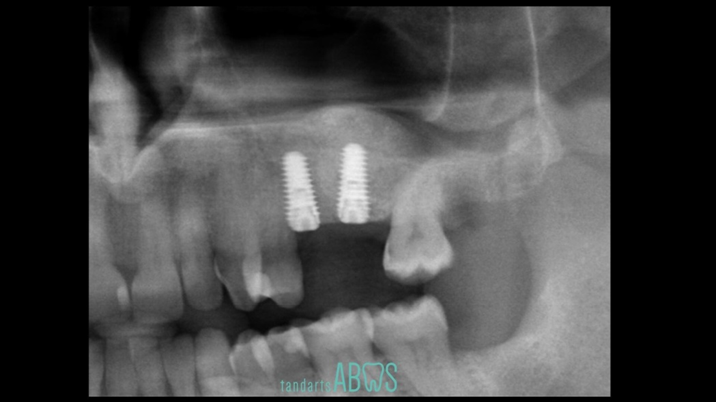

Clinical case: Delayed implant placement: sinus floor elevation by means of lateral

approach & implant placement with GBR

- Courtesy of Dr. Irfan Abas, Netherlands -